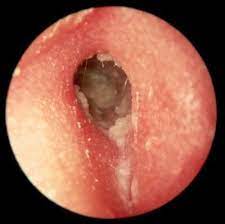

- عفونت قارچی گوش خارجی: این بیماری به اوتومایکوزیس هم معروف است. در این بیماری، قارچ هایی مانند آسپرژیلوس یا کاندیدا در مجرای گوش خارجی رشد می کنند. عواملی مانند دیابت، ضعف سیستم ایمنی و شرایط مرطوب می توانند این بیماری را تسهیل کنند. علائم این بیماری شامل خارش، ترشح، سوزش، درد و کاهش شنوایی هستند. ممکن است توده های سفید، سیاه یا سبز رنگ در مجرای گوش خارجی دیده شوند. درمان این بیماری با تمیز کردن مجرای گوش خارجی و قطره گوش حاوی ضد قارچ انجام می شود.